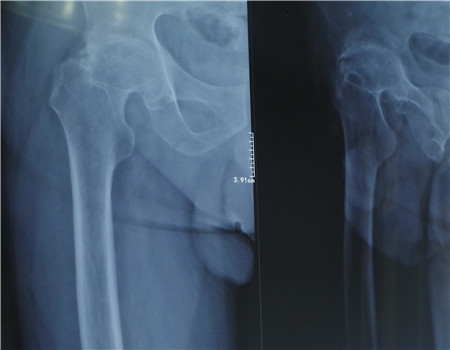

薛先生五年前无外伤诱因下感觉右髋疼痛,自己用药膏外敷、口服止痛药后,疼痛无明显好转,于是到当地医院就诊,拟诊为“腰椎间盘突出症”,给予骨盆牵引康复理疗,服用中药,疼痛并未缓解。一年前到南通市第三人民医院诊治,并给予抗结核治疗,关节结核是有好转,但右髋关节疼痛并未缓解。近半年来感觉右髋关节疼痛加重,僵硬,右腿变短,跛行,右腿也明显比左腿瘦小。

2月18日入院后,医务人员结合其病史,积极的完善了其他相关检查,初步诊断为右股骨头坏死、右髋关节骨性关节炎。根据薛先生的病情、影像资料及身体状况进一步明确诊断、排除手术禁忌症,经过详细的讨论及全面的评估后,科室制定了佳的治疗措施及手术方案。